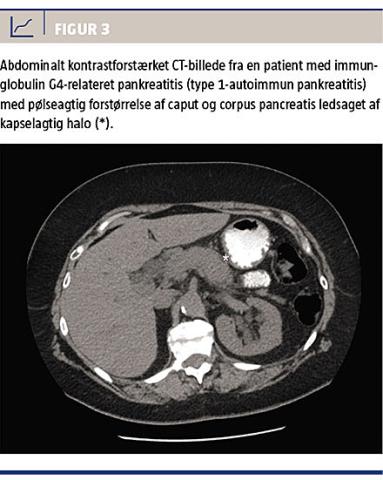

I pancreas er en pølseagtig forstørrelse sammen med en såkaldt peripankreatisk halo ved kontrastforstærket CT karakteristisk for den IgG4-relaterede type 1-AIP (Figur 3). En lokaliseret eller diffus organforstørrelse kan i mange tilfælde ses med både konventionel røntgenundersøgelse, kontrast-CT, MR- og

ultralydskanning. Billeddiagnostikken bør dog suppleres med grovnålsbiopsier for bedre at kunne skelne maligne fra IgG4-relaterede eller andre benigne læsioner [18]. IgG4-relateret periaortitis er ved CT karakteriseret ved en ensartet vægfortykkelse og signalforstærkelse i den sene fase efter kontrast. CT med kontrast af thorax og abdomen inklusive det lille bækken anbefales mht. andre, eventuelle synkront